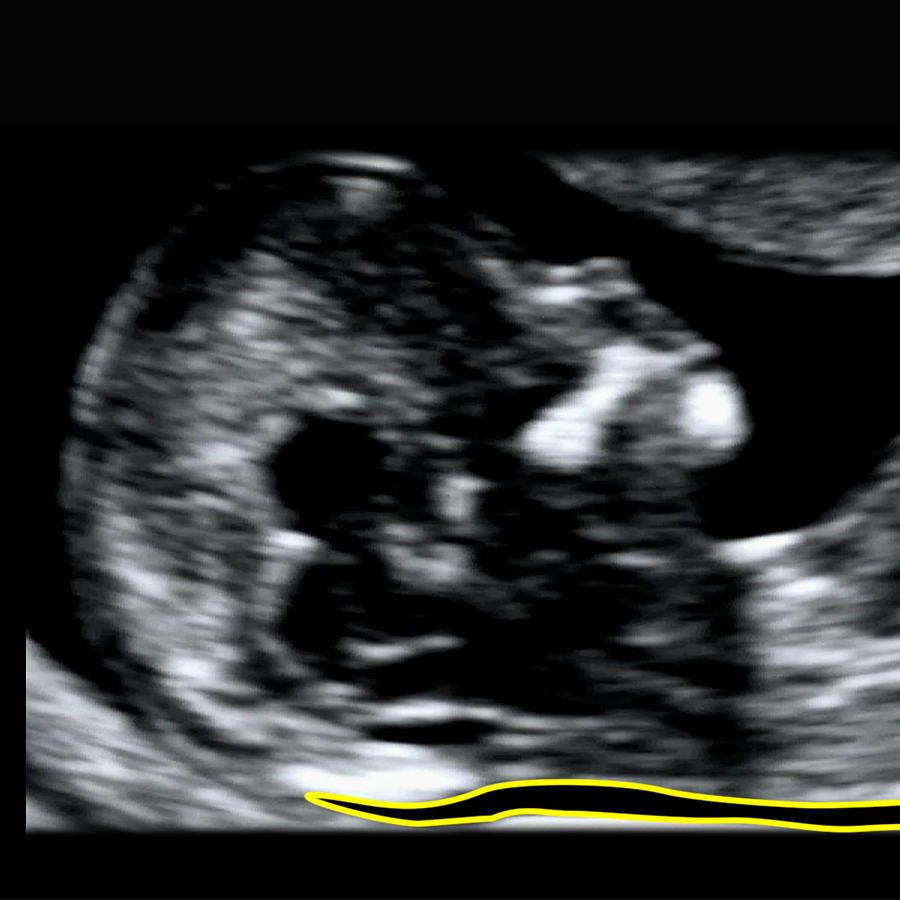

The cut-off for what is called “increased” NT varies between countries and research groups. Most researchers use the 95th centile as the threshold for increased NT, because this is the standard approach for almost every fetal measurement in medicine. NT also rises naturally as the baby grows, so what is “normal” always depends on your baby’s size.

As a simple rule of thumb, between 11 and 14 weeks an NT under about 3.5 mm is usually considered within the expected range. Measurements of 3.5 mm or more are often labelled “increased” or “high”, but in reality they represent an abnormal NT because they are above the 99th centile. At around 10 weeks’ gestation, the abnormal cut-off is lower, at about 2.5 mm, because the baby is still very small and NT is closely related to fetal size.

Your baby’s result is always interpreted in context, taking into account the exact crown–rump length, gestational age and, where relevant, the associated blood test results.

Increased NT Cut-off day by day chart.